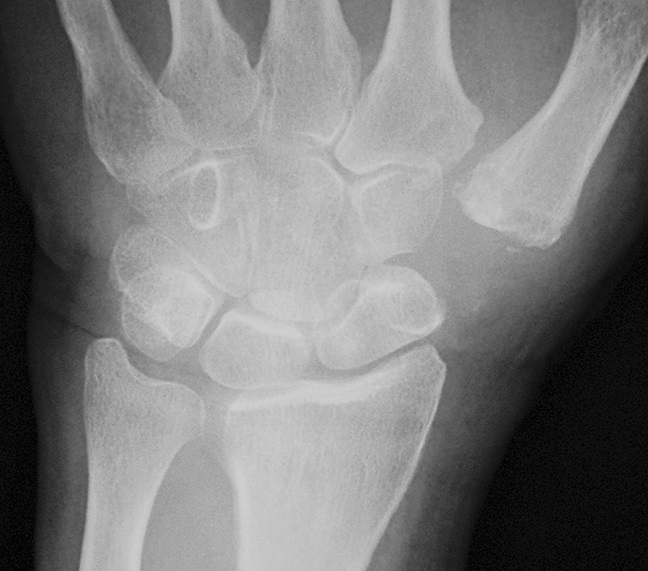

A patient with arthritis of the thumb CMC joint in both hands.

Reproduced from Rabinovich RV, Potlasch, DB, Shin DD, Beldner S: Thumb Carpometacarpal Instability. J Am Acad Orthop Surg. 2021;29(22):943-950. Reprinted with permission from Eaton R, Littler JW: Ligament reconstruction for the painful thumb carpometacarpal joint. J Bone Joint Surg Am. 1973;55:1655-1666.